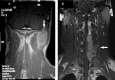

Findings: Initially, the patient had a mass in the left posterior neck region and later developed a large extradural mass at the C3-C7 level. The masses were excised, and the histological findings led to a diagnosis of small cell osteosarcoma. He underwent chemotherapy and radiation therapy. He experienced numbness in his left leg; subsequently, the numbness slowly spread up the thigh to the left side of the abdomen. When pinched in the numb area on the left side of the body, he felt as though he had been pinched in both that area and the corresponding area on the right side. A magnetic resonance imaging scan showed an enhancing lesion in the right side of the cord at the C6-C7 level.